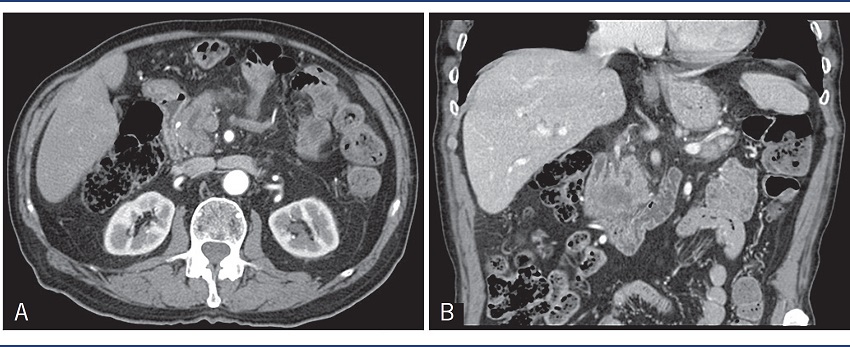

All our patients had evaluation by CT scan for better surgical approach (Figure 1). None of our patients had elevation of serum calcium levels along their clinical course.

A) axial cut: Wirsung dilation due to a cephalic pancreatic mass; B) coronal cut: cephalic pancreatic mass.

CT: computed tomography.